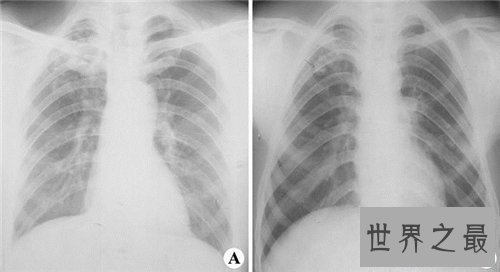

患者在病情重大者会出现气喘,全身乏力,体重减轻,心慌出虚汗,杵状指及唇甲紫绀。血常规反省,发现细菌感染时,中性粒细胞增高,白细胞计数多显著增高,若为病毒感染时,白细胞多失常或低下。X线反省反省发现两肺纹理增重,沿支气管散布散在小片状或点状浸润暗影。